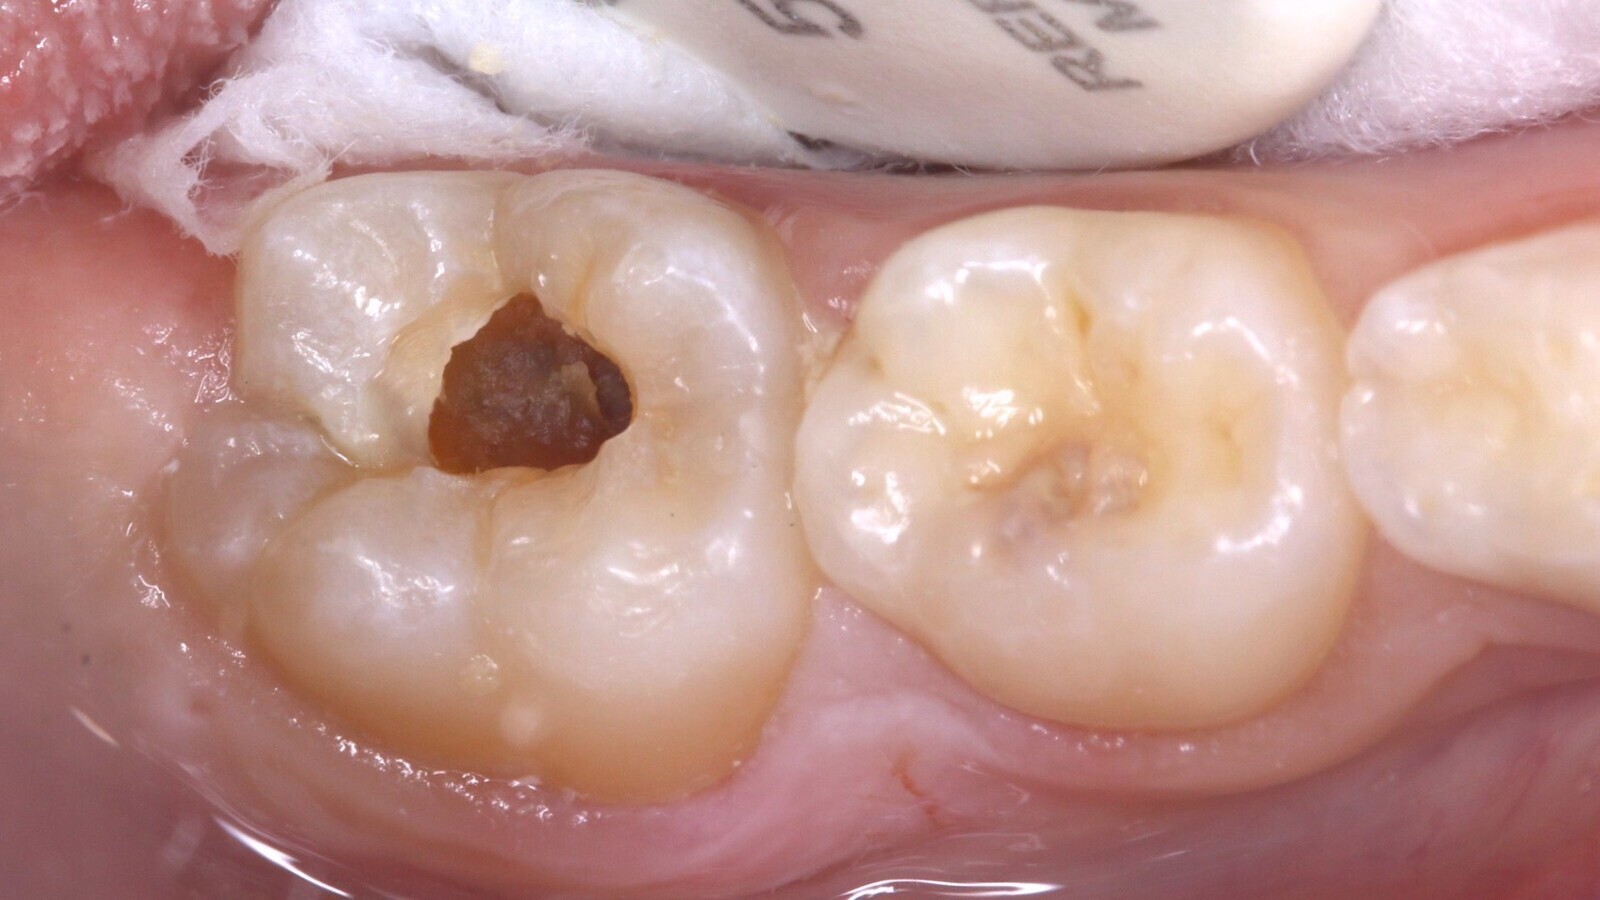

Por la severidad de la lesión, sin una cavidad evidente, se decide realizar una remoción de esmalte con alta rotación utilizando fresas diamantadas con la finalidad de acceder a la dentina cariada con instrumentos manuales, complementados con un agente enzimático a base de papaína (Papacarie Duo, Formula & Ação) (Fig. 3).

Fig. 3. La remoción de esmalte con fresas diamantadas para acceder a la dentina cariada con instrumentos manuales se complementó con la aplicación de un agente enzimático a base de papaína.